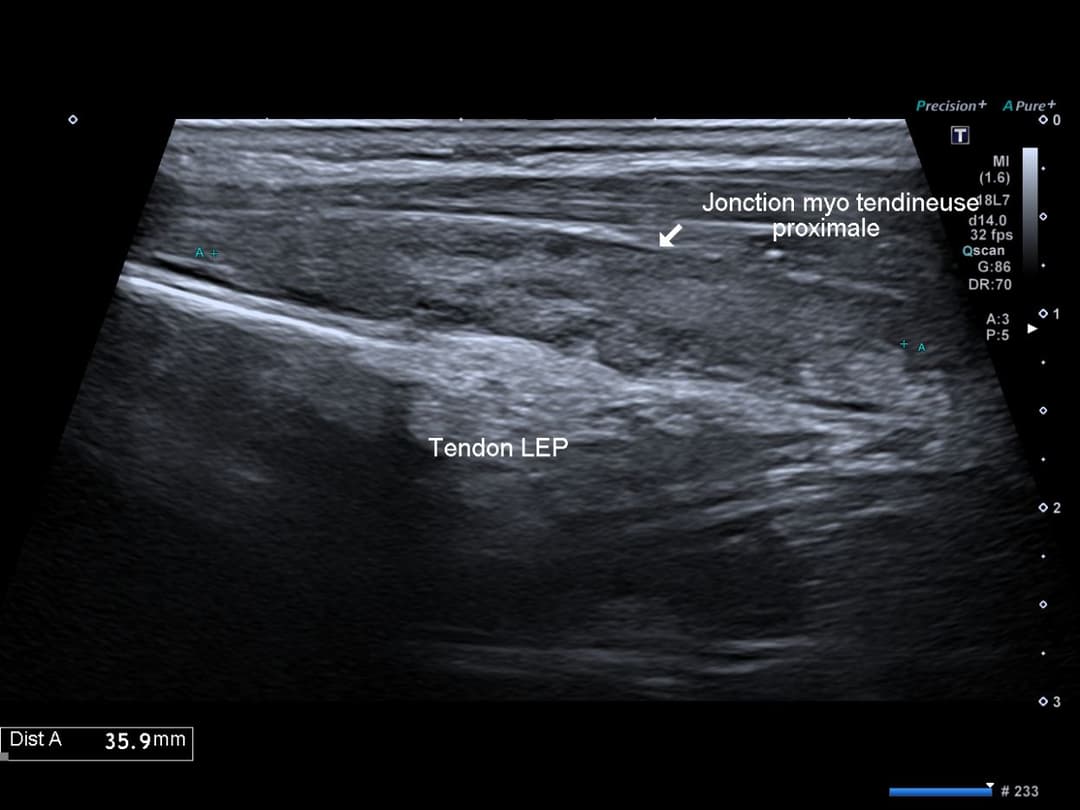

Coupe sagittale au niveau du croisement distal, épaississement fusiforme du tendon avec désorganisation architecturale

Le DIS se produit au niveau du croisement entre le tendon long extenseur du pouce (EPL) du troisième compartiment et les tendons extenseurs radiaux du carpe long et court (ECRL et ECRB) du deuxième compartiment, juste distal au tubercule de Lister.